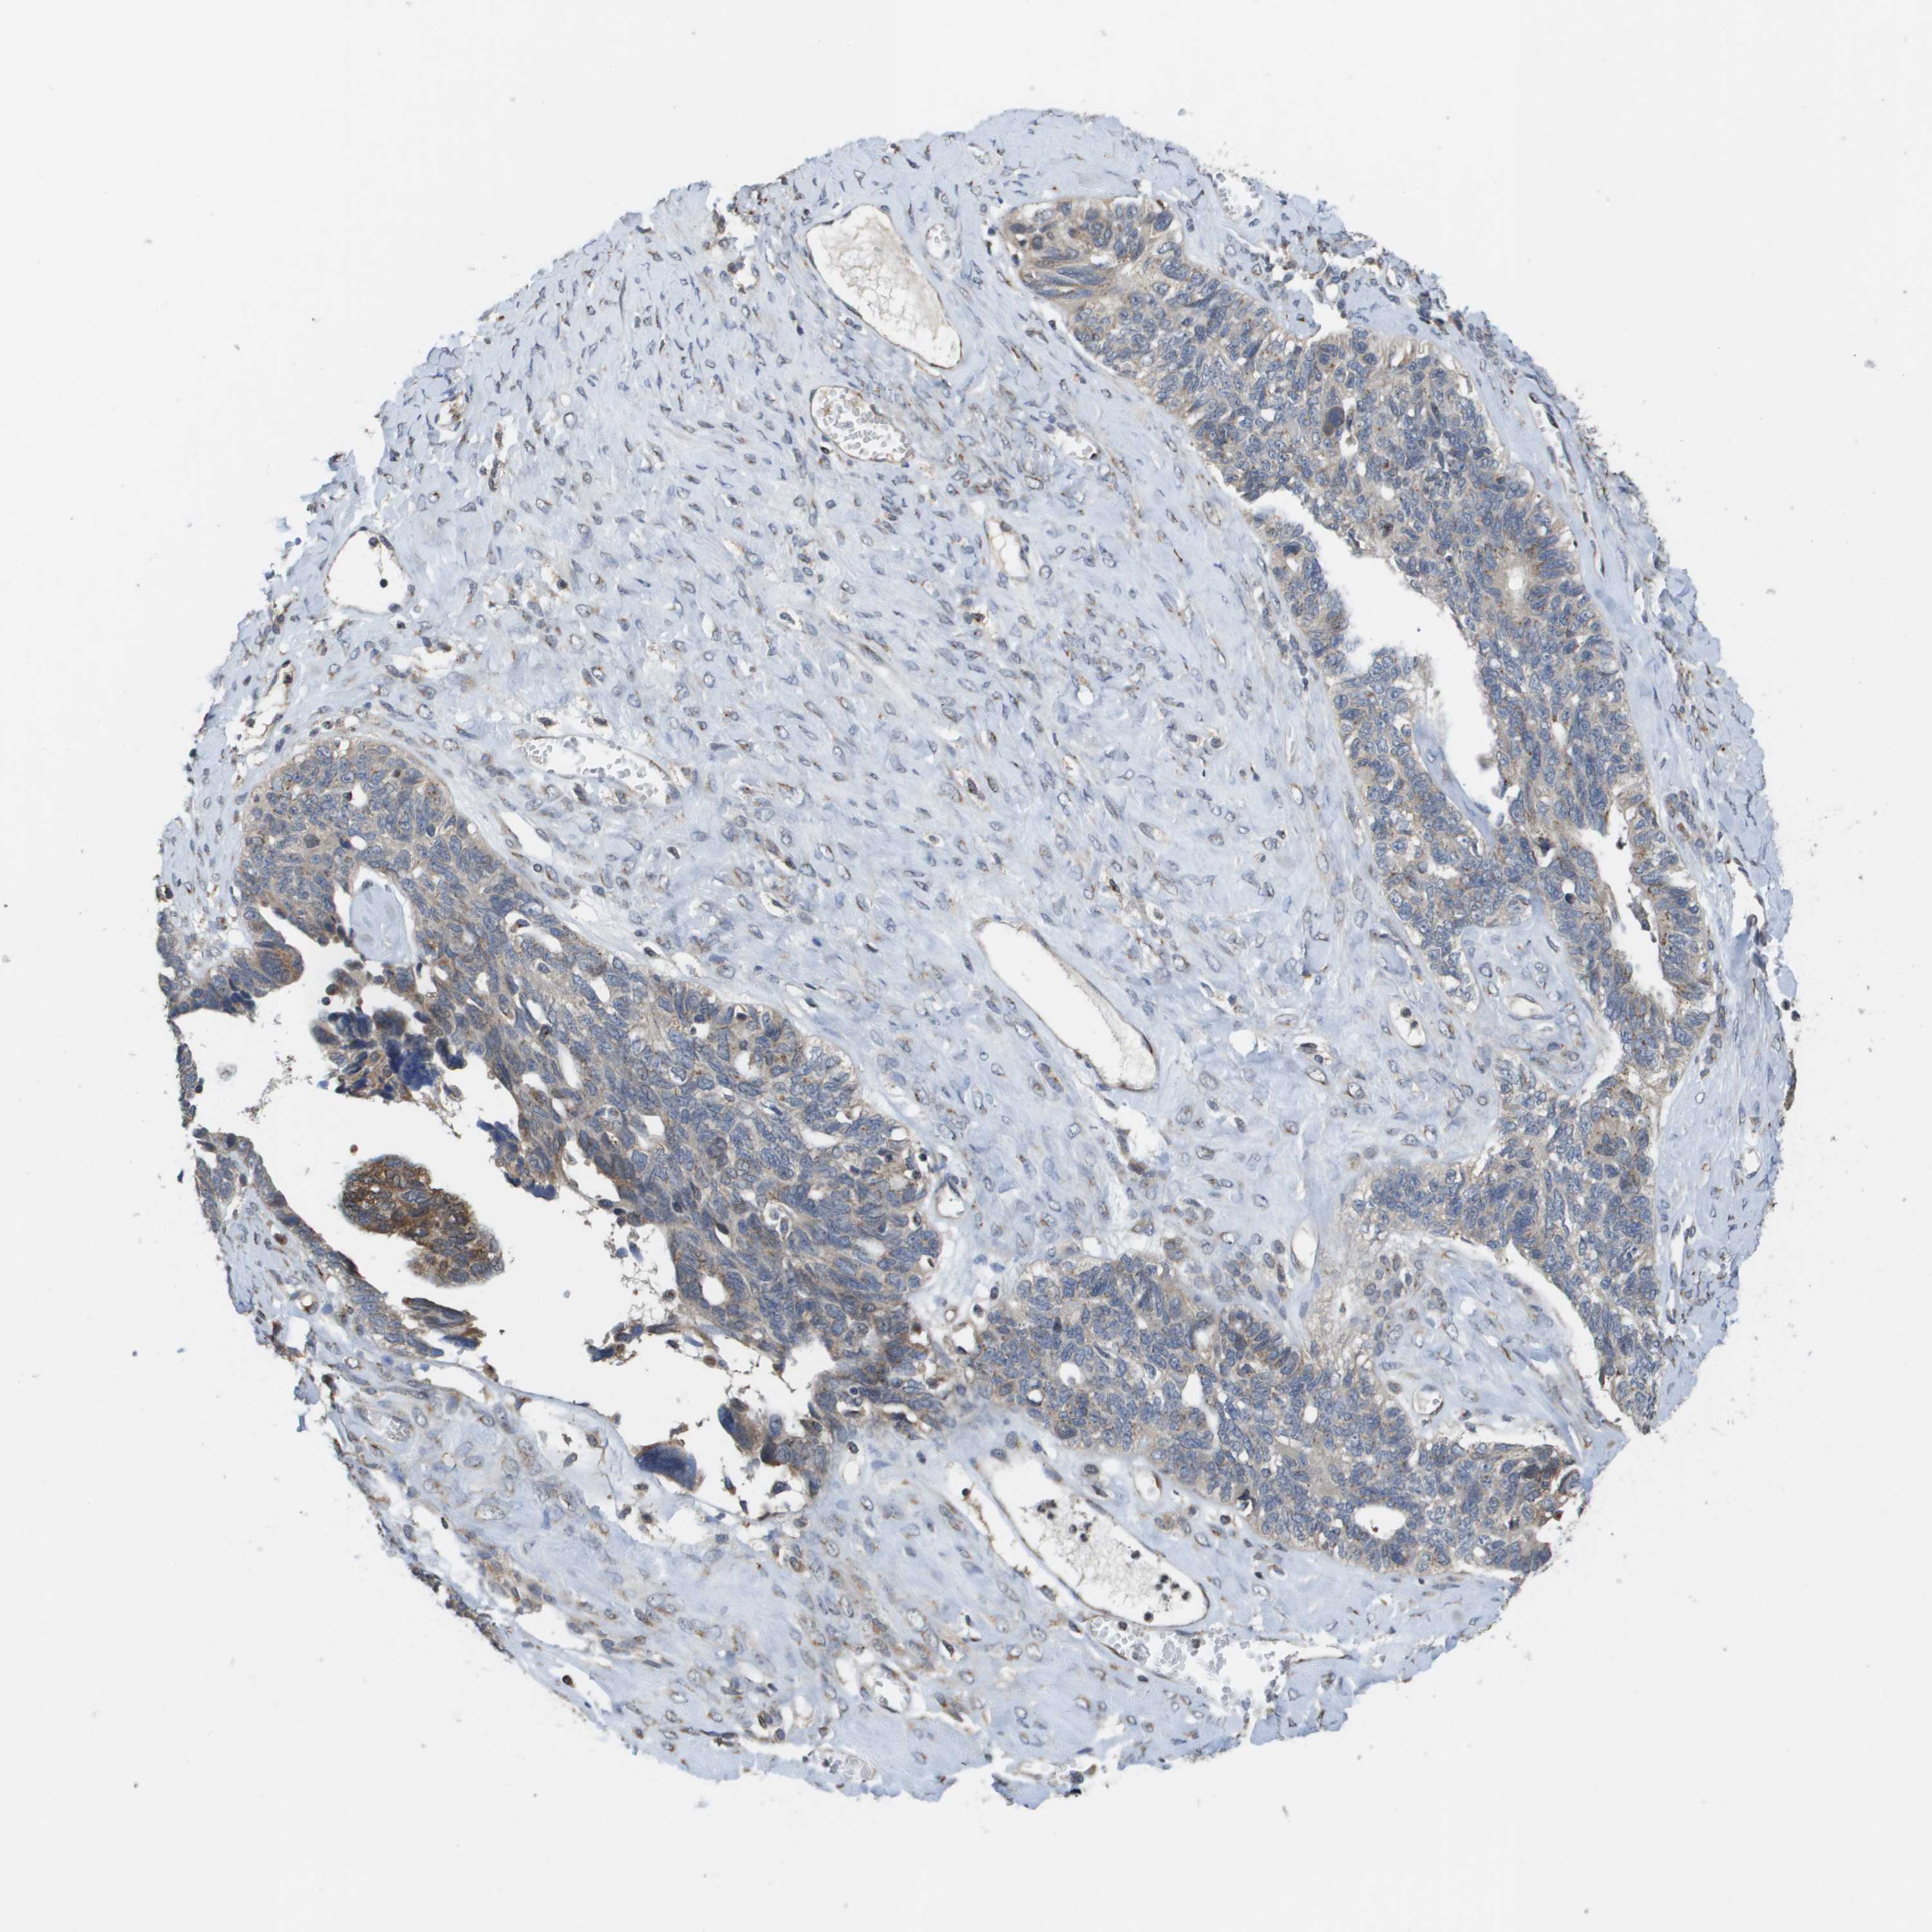

OVARIAN CANCER - Protein expressioni

A mouse-over function shows sample information and annotation data. Click on an image to view it in a full screen mode. Samples can be filtered based on level of antibody staining by selecting one or several of the following categories: high, medium, low and not detected. The assay and annotation is described here.

Note that samples used for immunohistochemistry by the Human Protein Atlas do not correspond to samples in the TCGA dataset.

Antibody stainingi

Antibody staining in the annotated cell types in the current human tissue is reported as not detected, low, medium, or high, based on conventional immunohistochemistry profiling in selected tissues. This score is based on the combination of the staining intensity and fraction of stained cells.

Each image is clickable and will lead to virtual microscopy that enables deeper exploration of all samples and also displays staining intensity scores, fraction scores and subcellular localization as well as patient and tissue information for each sample.

Antibody CAB017027

Staining

Medium

Low

Not detected

Carcinoma, NOS

Carcinoma, endometroid